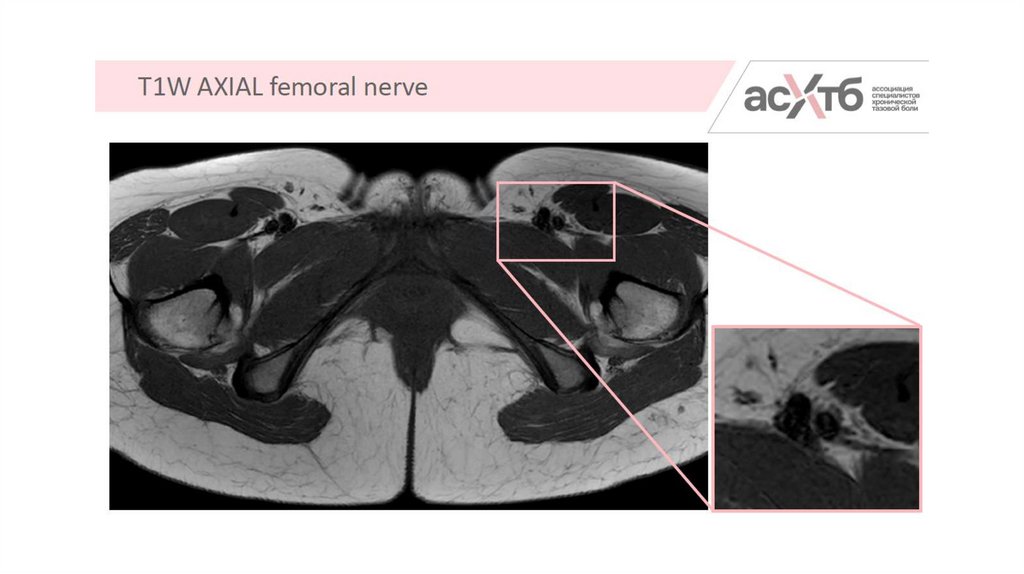

5.

7. МР-нейрография

8. Режимы